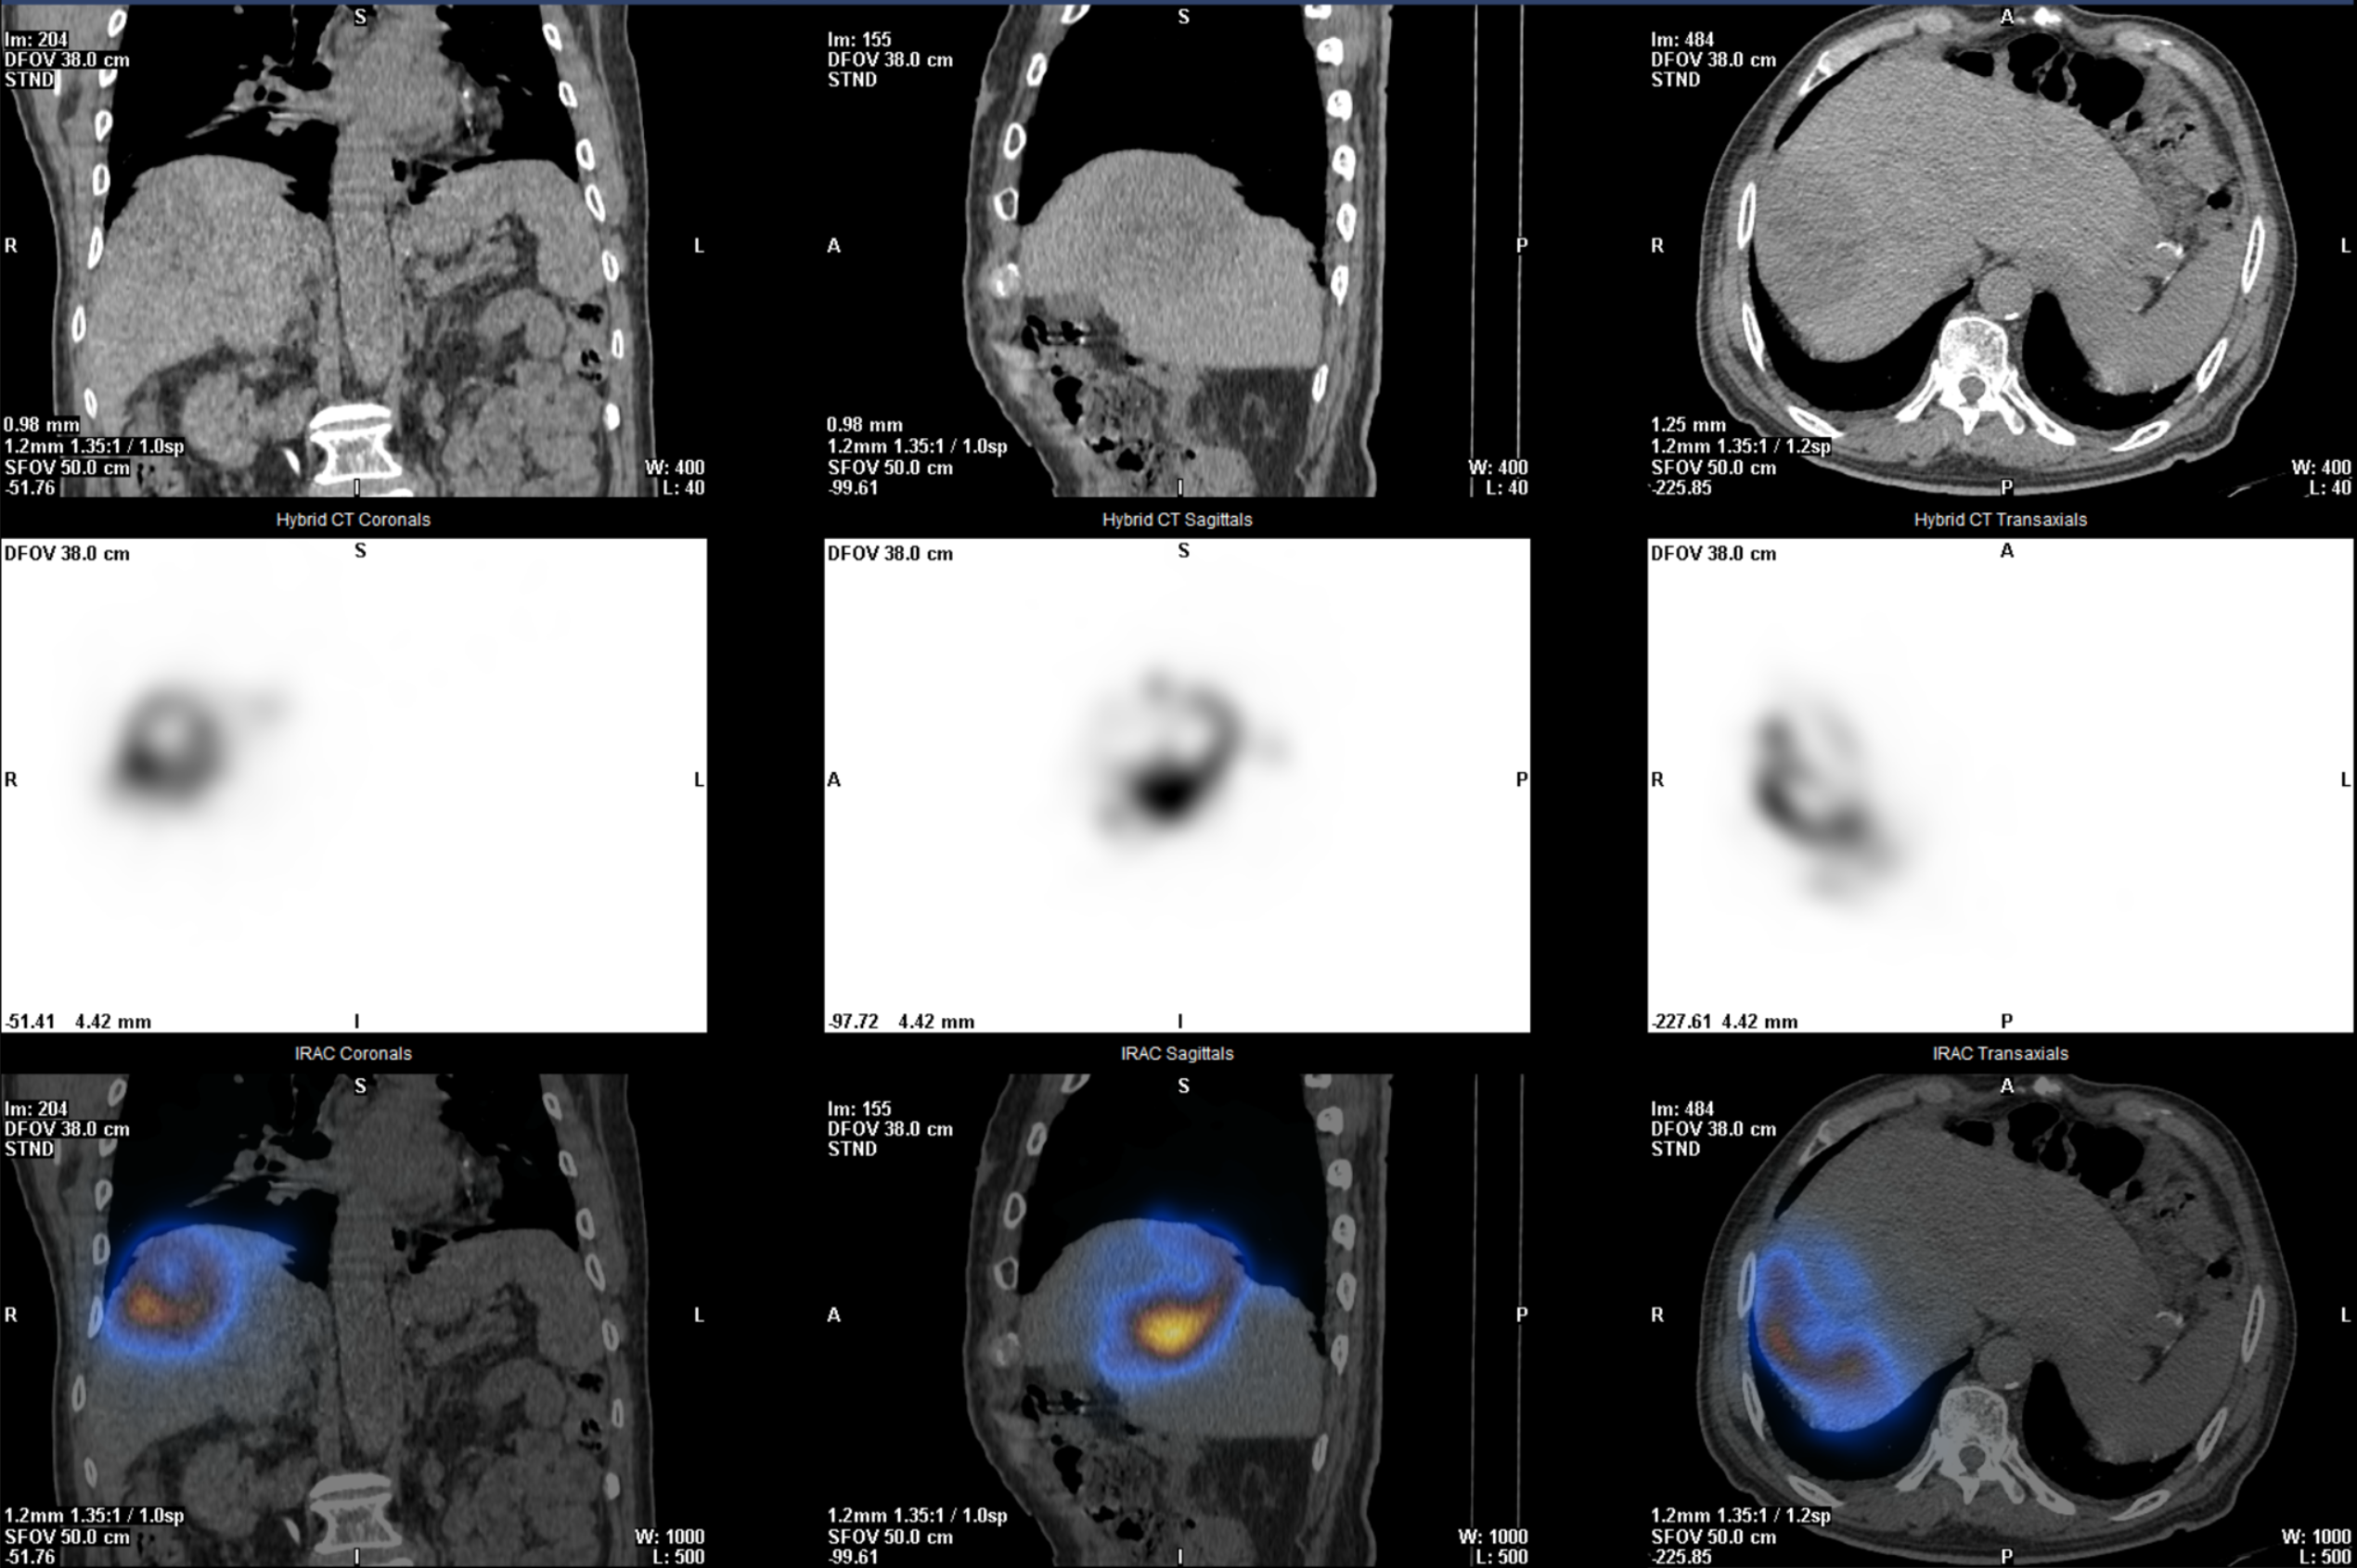

术前影像资料

术前:MAA验证,患者符合Y90手术指征